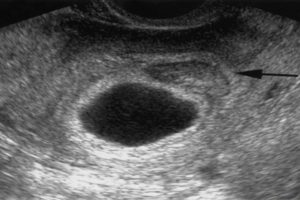

Низкое расположение плодного яйца на ранних сроках беременности

Самый ранний срок, когда можно достоверно увидеть беременность на УЗИ, – пятая неделя.

Хороший врач на качественной аппаратуре сможет рассмотреть плодное яйцо, эмбрион в нем (он будет выглядеть как маленькая темная полоска длиной 3-5 мм), околоплодные воды; измерить его, оценить форму и прослушать сердцебиение эмбриона. Многоплодную беременность с уверенностью можно будет увидеть на более поздних сроках – примерно на 8-9 неделе.

Если врач во время ультразвукового исследования сообщает, что видит в полости матки плодное яйцо — женщину можно поздравить, ведь через 9 месяцев она станет мамой. Установить наличие плодного яйца можно уже на 7-9 день задержки менструации.

Если плодное яйцо в матке – значит беременность нормальная, маточная. Специалист сразу же определит размер плодного яйца, его форму и расположение. Кроме этого, обратит особое внимание, не имеет ли место отслойка или другие патологические состояния.

Плодное яйцо – овальное или круглое тело диаметром в несколько миллиметров. Диаметр плодного яйца замеряется во время первого же УЗИ. Учитывая его размеры, специалист может установить срок беременности. Но в некоторых случаях погрешность в определении составляет 1-1,5 недели. Поэтому врач, пытаясь установить срок, учитывает также показатели копчико-теменного размера.

плодное яйцо выглядит как образование в виде шара или овала. Уже в 5-6 недель желточный мешок, который обеспечивает питание эмбриона и выполняет кроветворную функцию на ранних стадиях развития эмбриона, похож на пузырек внутри полости плодного яйца.